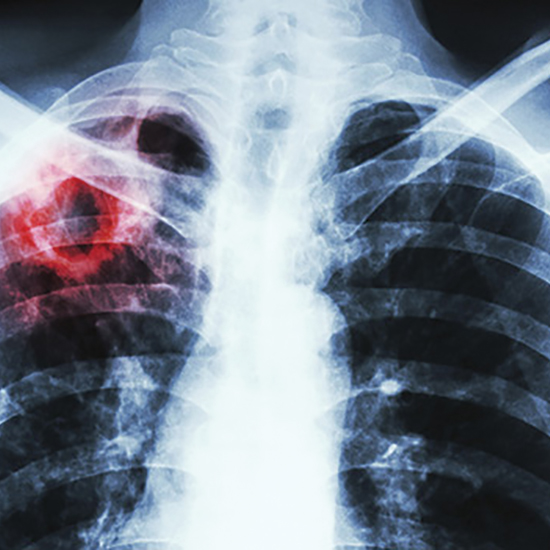

Розширення програмного управління у сфері профілактики та лікування латентної туберкульозної інфекції (ЛТІ) є важливим кроком до подолання епідемії туберкульозу.

Проте в Україні цей напрям ще потребує оптимізації, наголошують у Центрі громадського здоров’я Міністерства охорони здоров’я (МОЗ) України.